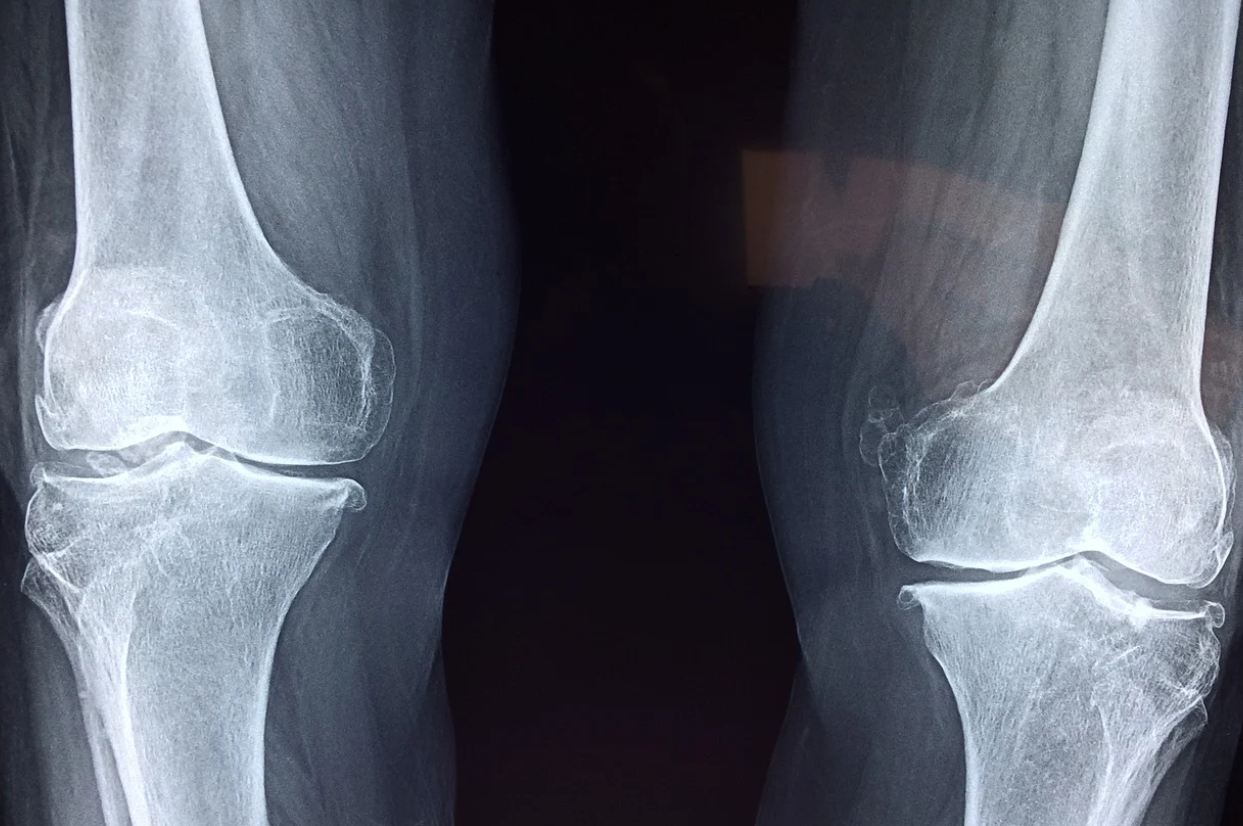

꼬부랑 할머니의 원인

최근 꼬부랑할머니의 빈도가 현저하게 줄어들었다. 입식부엌이 생기면서 쪼그려앉아 가사노동을 하지 않고, 냇가에 쪼그려서 빨래를 하지 않게 되었다. 밭에서 쪼그려 밭일도 하지 않게 되었다. 예전에는 쪼그린 자세로 10년, 20년, 30년 일하다 보니 허리가 굽는 근골격계질환이 생겼을 가능성이 높았다.

아무리 쉬운 작업이라고 장기간 쪼그리는 자세 등에 노출되면 근골격계 질환이 생길 수 밖에 없다고 하니 단순 노동이라도 중간중간 스트레칭을 해줘야겠다.